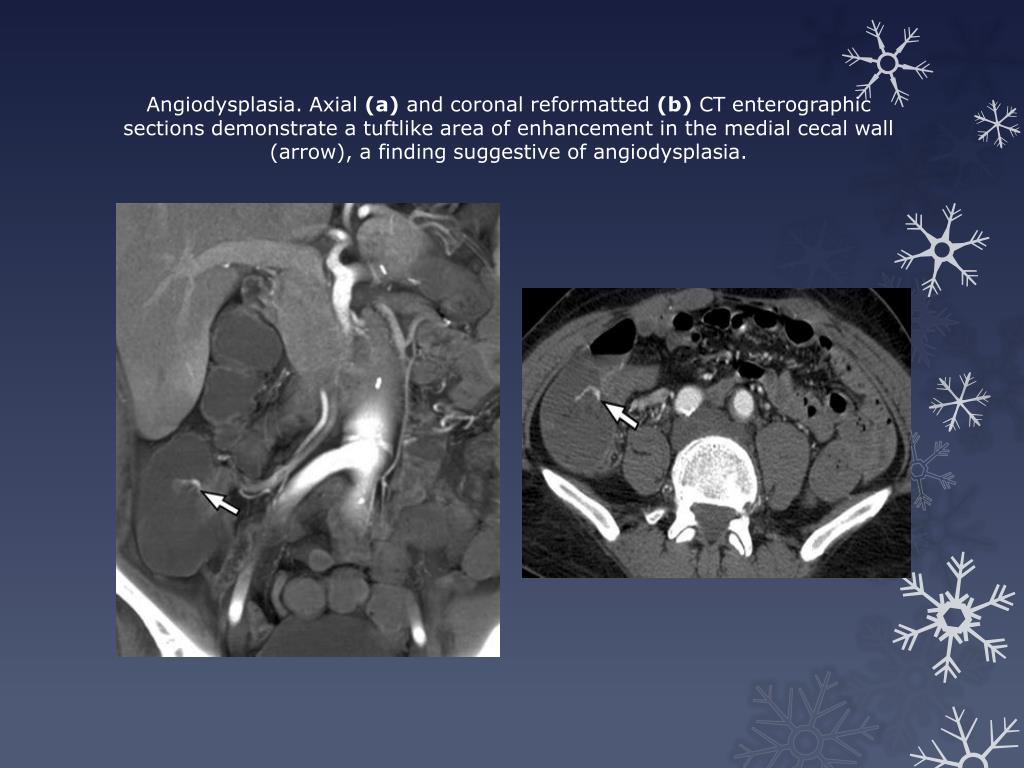

40. Angiodysplasia is the most common cause of occult GI tract bleeding. • The structural abnormality usually appears as an avidly enhancing plaque or nodule during the enteric phase and fades during the delayed phase. Less commonly, it might manifest as a focal area of enhancement or an associated early draining vein during the arterial phase. • Other causes of GI tract bleeding that may be detected at CT enterography include various types of vascular malformations, neoplasms, and Meckel diverticulum . • Small bowel tumors such as leiomyoma and gastrointestinal stromal tumor (GIST) also may be sources of occult GI tract bleeding.

41. Angiodysplasia. Axial (a) and coronal reformatted (b) CT enterographic sections demonstrate a tuftlike area of enhancement in the medial cecal wall (arrow), a finding suggestive of angiodysplasia.